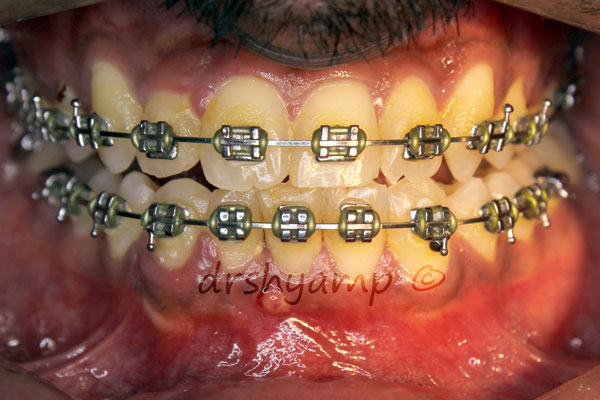

proclined anterior teeth

-

proclined anterior teeth

-

Correction of proclined anterior teeth

-

proclined anterior teeth

Correction of proclined anterior teeth